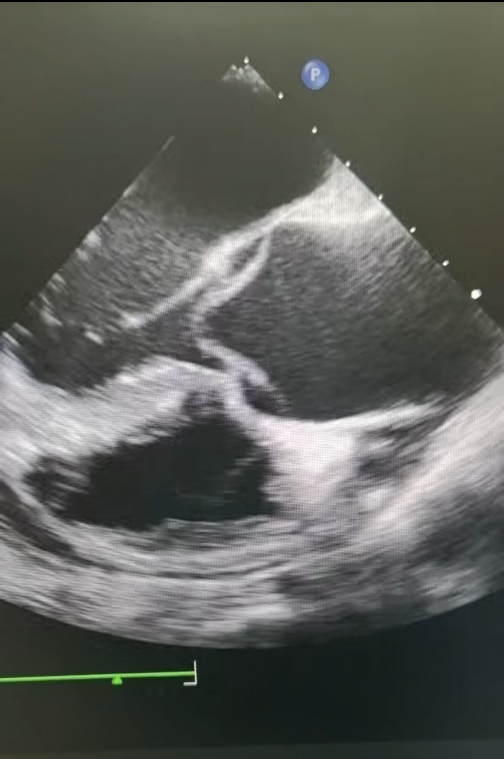

与此同时,武慧蓉医生已在手术室为心脏移植受体患者行经食道超声,心脏移植术中食道超声是不可或缺的“导航仪”,通过将超声探头置入食道,可近距离获取高分辨率的心脏影像,实时监测心脏各腔室、瓣膜及血管的形态与功能,精准指导手术操作,及时发现术中心包积液、血管吻合口异常等,确保手术安全高效推进。

正当心脏移植进行时,两台主动脉夹层急诊手术的食道超声配合工作也在紧张有序地开展。主动脉夹层被称为“心血管疾病中的炸弹”,发病急、死亡率高,48小时内死亡率高达50%,每延迟一分钟,患者的生命就多一分危险。通过食道超声检查,武慧蓉医生正在仔细检查患者夹层撕脱累及的范围,冠脉是否受累,以及主动脉瓣膜情况。